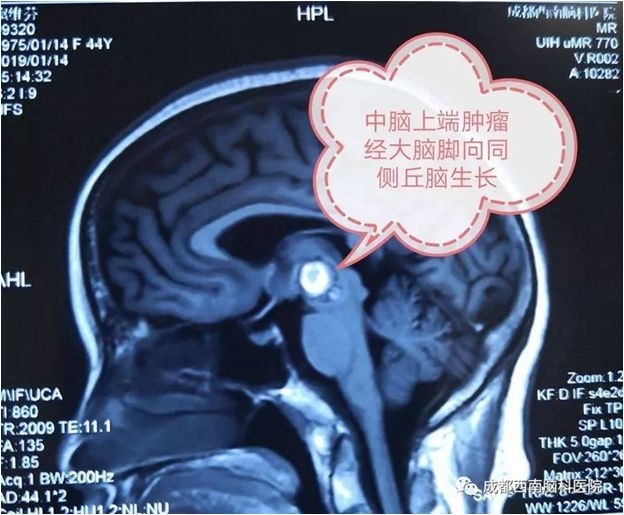

中脑海绵状血管瘤手术

术前